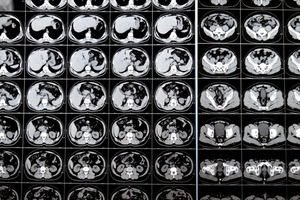

CT scan and MRI/MRCP

These provide detailed information about the extent of the tumour, its involvement with the liver, bile ducts, blood vessels, and lymph nodes, and help determine surgical resectability.